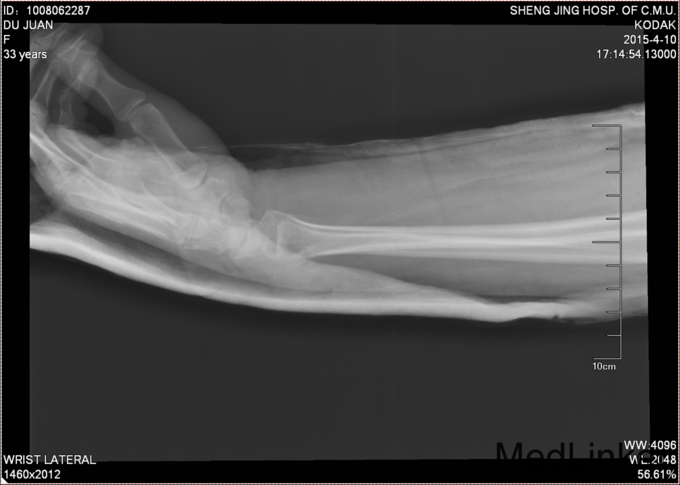

术后给予患者止疼消肿等对症治疗,石膏固定后2周后给予复查腕关节正侧位DR,位置良好,更换功能位短石膏。